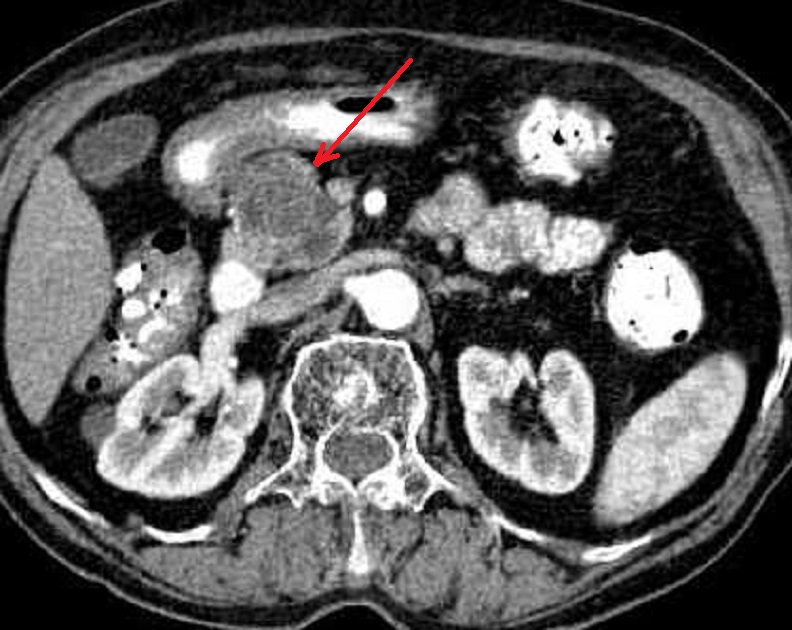

Aspect radiologique du cystadenome

sereux multikystique de la tete du pancreas . La

tumeur est comporte par des kyste a moindre 2cm a

hypodense , de contour et cloison septal interne

sont nette , Image radiologique TDM non contrast

intraveineuese , coupe axiale . |